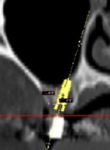

インプラント治療が始まってすでに40年の歴史を持っており、適切な診断としっかりとした治療計画のもとに、正確な手術を行えば非常に信頼性の高い治療法です。

ただし、患者さまの口の中やあごの骨の状態によってさまざまなアプローチが必要となるため、担当医の経験と熟練したテクニックが必要になります。